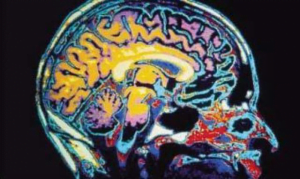

Long-Term Side Effects of Traumatic Brain Injury

More than three million Americans are living with traumatic brain injury (TBI). This condition is linked to many physical, cognitive and emotional problems. It often has sexual side effects that are associated with marital instability, identity problems and low self-esteem.

Approximately 1.4 million individuals sustain a traumatic brain injury each year in the United States. TBI is also a major cause of death and disability worldwide, especially in children and young adults. Males sustain traumatic brain injuries more frequently than do females.